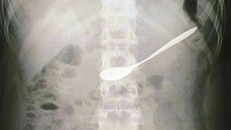

Cứu cô gái 20 tuổi đi uống cà phê nuốt chiếc thìa vào bụng

Một cô gái 20 tuổi phải nhập viện cấp cứu sau khi đi uống cà phê với bạn và nuốt cả chiếc thìa vào bụng.